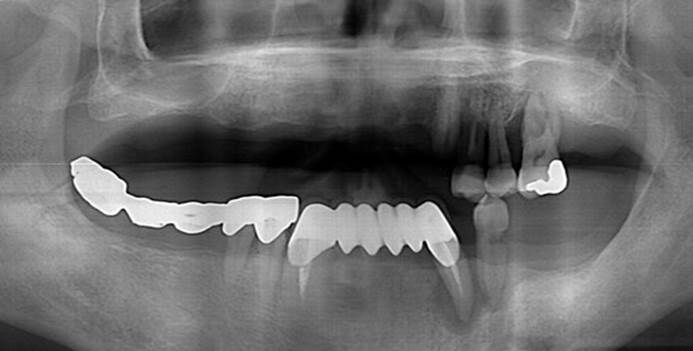

Clinical case: AFull transition from natural teeth to all-on-6 bridges

with AnyRidge implants

- Courtesy of Dr. Rabih Abi Nader, UAE -